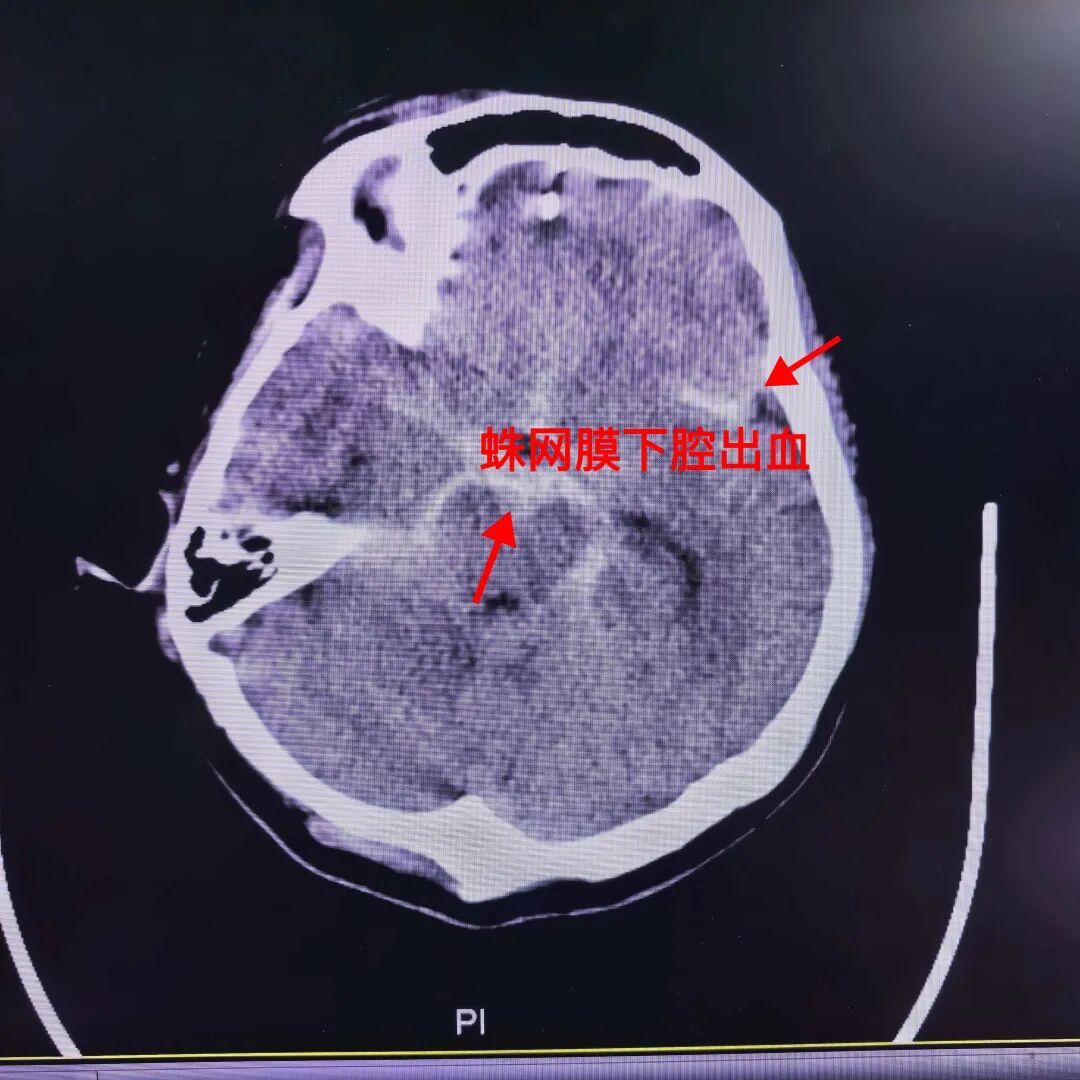

急诊CT检查很快有了结果:刘阿姨是“蛛网膜下腔出血”。接诊的神经外科医生苏稳解释,这就像大脑表面的血管破了,血液漏到了大脑和头骨之间的空隙里,属于凶险的脑出血,稍有延误就可能危及生命。